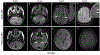

Aquaporin-4-IgG positive neuromyelitis optica spectrum disorder (AQP4+NMOSD) and myelin-oligodendrocyte glycoprotein antibody-associated disease (MOGAD) are antibody-associated diseases targeting astrocytes and oligodendrocytes, respectively. Their recognition as distinct entities has led to each having its own diagnostic criteria that require a combination of clinical, serologic, and MRI features. The therapeutic approach to acute attacks in AQP4+NMOSD and MOGAD is similar. There is now class 1 evidence to support attack-prevention medications for AQP4+NMOSD. MOGAD lacks proven treatments although clinical trials are now underway. In this review, we will outline similarities and differences between AQP4+NMOSD and MOGAD in terms of diagnosis and treatment.